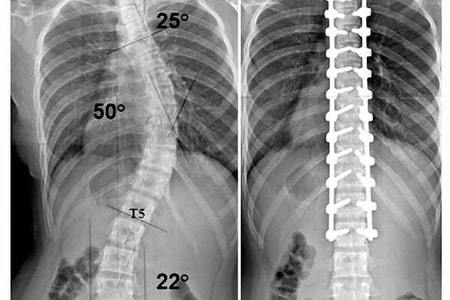

Рентгенологическое исследование необходимо для изучения костно-хрящевых и скелетных аномалий.

На фото хорошо видны кости, виден рельеф и состояние твердых тканей. Опухоли, воспаления, гематомы отмечаются тенями и штриховкой.